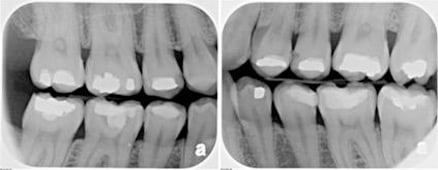

Bitewing X-Rays

There are various types of X-ray.  Some show one or more teeth and their roots, while others can take a picture of several teeth at once.  The most common X-rays are small ones called a Periapical radiograph or a set of Bitewings, which are taken regularly to keep a check on the condition of the teeth and gums, showing the roots and surrounding area.  The larger X-ray is called a Panoral radiograph and shows the whole mouth including all the teeth and the bone structure that supports the teeth.